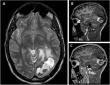

Chinese Neurosurgical Journal Study Explores Diagnostic Role of Brain Biopsy in Leukemia with CNS Involvement

Chinese Neurosurgical Journal Reports Rare Hematoma Following Cyst Formation After AVM Radiosurgery